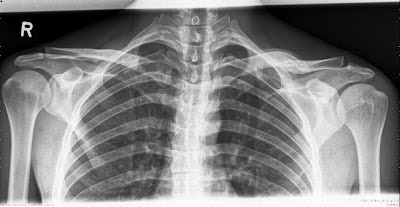

Csütörtökön voltam a "váll specialista" dokinál, aki a vitt röntgenfelvételek láttán és némi kézgyakorlat tesztelés után megállapította, hogy a szalag minimál meg van nyúlva, elszakadva egész biztosan nincs, minden ok. Edzeni lehet mindent amíg nem fáj. Ha fáj, stop! És ő mondta, lehet már eleve kicsit nyúltabb volt a kulcscsontom furcsasága miatt az a rész....

Egyáltalán nem fáj meg semmi, de kb 1-2mm-el feljebb áll a kulcscsontom vége mint a jobb vállamban. Lehet mindig ilyen volt a kulcscsonttörés óta, nem tudom... sosem tűnt fel...de szerintem nem.

A röntgenképet beszúrom ide a végére:

| luxation acromioclavicular joint, tossy 1 |